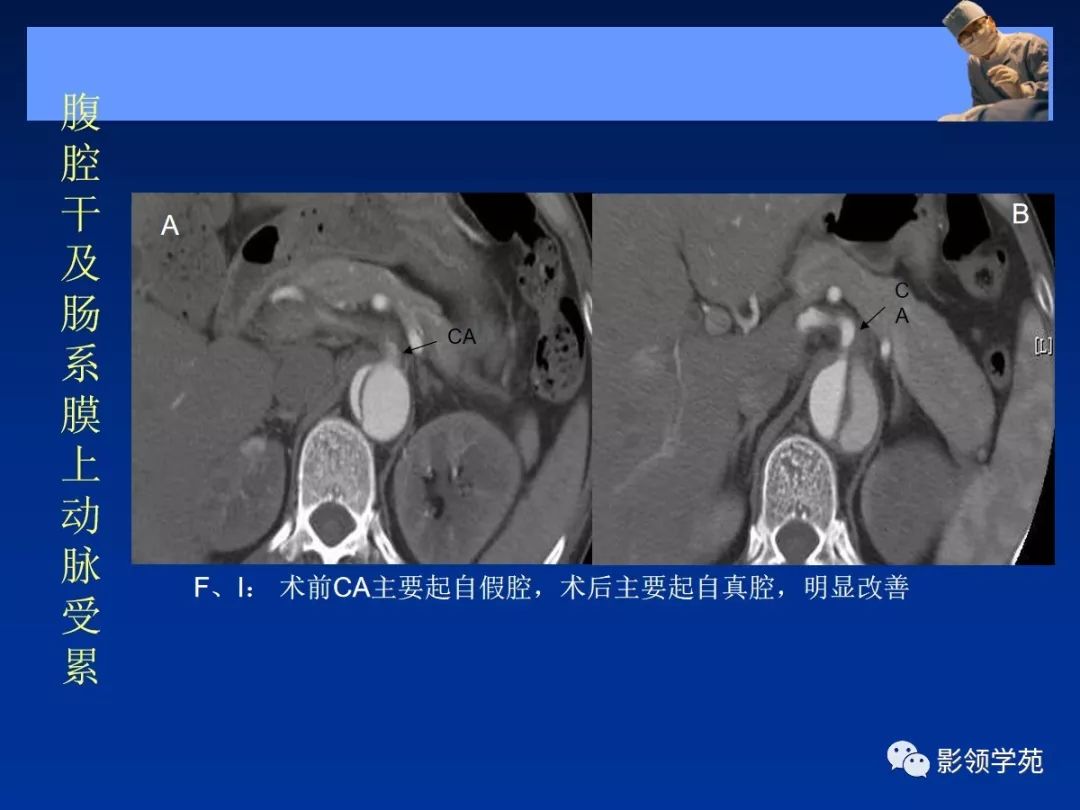

- 主动脉夹层(aortic dissection, AD)